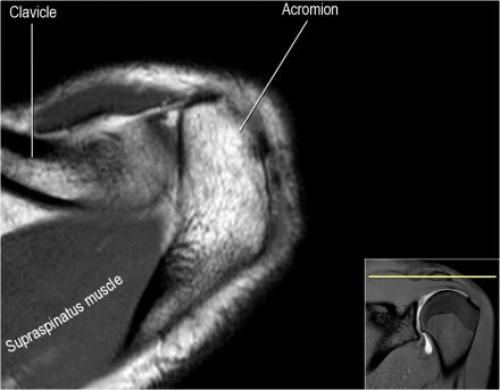

Хилл-Сакса мрт. Нормальная анатомия плечевого сустава в аксиальных изображениях и контрольный список.

- поищите os acromiale, акромиальную кость (добавочная кость, расположенная у акромиона)

- обратите внимание что ход сухожилия надостной мышцы параллелен оси мышцы (это не всегда так)

- обратите внимание что ход сухожилия длинной головки двуглавой мышцы в области прикрепления направлен на 12 часов. Область прикрепления может быть различной ширины.

- обратите внимание на верхние отделы суставной губы и прикрепление верхней плече-лопаточной связки. На данном уровне ищется SLAP-повреждение (Superior Labrum Anterior to Posterior) и варианты строения в виде отверстия под сутавной губой (sublabral foramen - подгубное отверстие). На этом же уровне по задне-боковой поверхности головки плечевой кости визуализируются повреждение Хилл-Сакса.